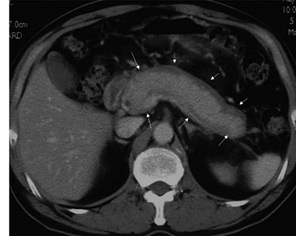

自己免疫性膵炎のCT画像: びまん性に膵臓が腫大(ソーセージ様、たらこ様と形容される)。膵臓に被膜様構造(黒い縁取り)がみられ、自己免疫性膵炎の典型的所見。